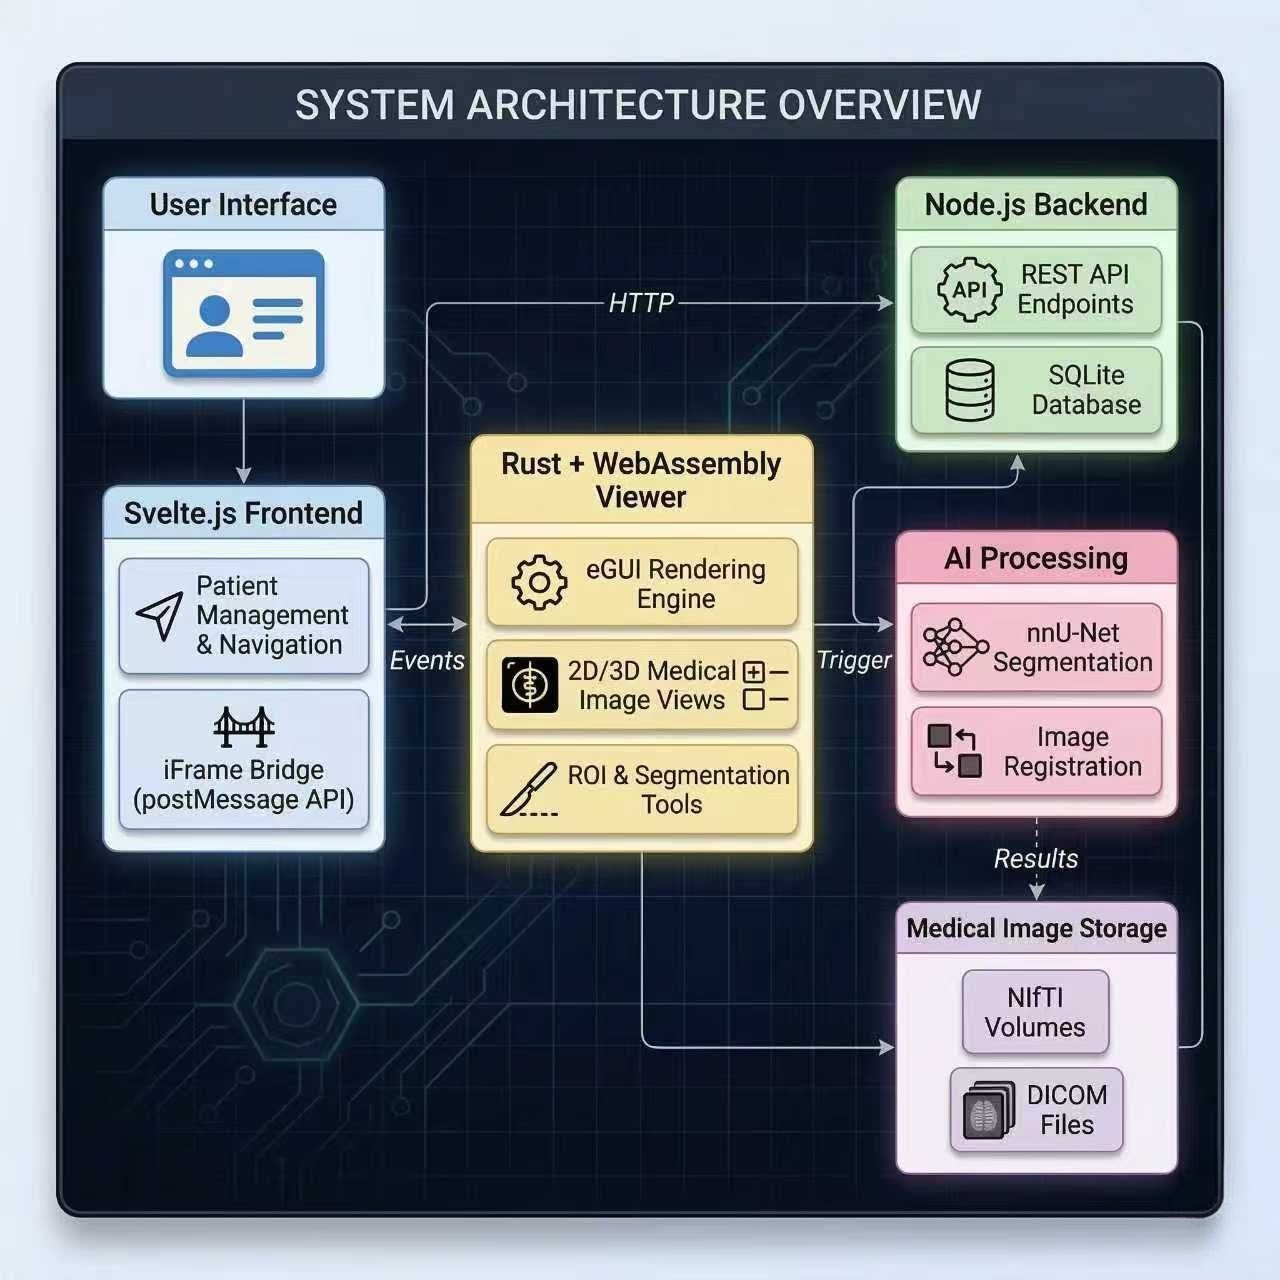

AI-Powered Stereotactic Radiosurgery Platform

Revolutionizing brain metastasis treatment with automated lesion detection, segmentation, and multi-course tracking. Built for radiation oncologists who demand precision.